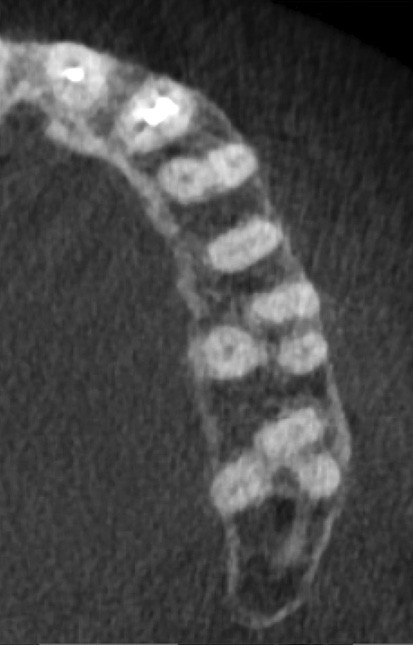

L’utilisation du scanner, et maintenant du CBCT, bouleverse l’idée très radiographique que nous avions du système canalaire.

En effet, la culture endodontique, fondée sur les critères radiographiques, a fait oublier les études de Hess et Zurcher (1925) qui mettent en évidence la complexité du système endo-canalaire [1]. Ce système présente une cavité principale (par exemple, le canal principal) ainsi que des canaux accessoires/latéraux. 25 % de ces microcanaux peuvent être interconnectés les uns aux autres, avec une densité plus importante de ramifications dans la région apicale du canal principal [2].

Rebondissant sur l’imagerie 3D et la mise en évidence des anatomies canalaires complexes, Peters, en 2001, décrit l’insuffisance instrumentale dans le traitement endodontique, et montre que 35 % des surfaces sont intactes après préparation canalaire correctement menée [18].

Endal, en 2011, montrait également, en utilisant le micro CT Scanner, l’insuffisance de nettoyage des isthmes inter-canalaires à nos techniques conventionnelles [19]. L’utilisation du laser Er:YAG devenait alors incontournable dans le nettoyage de ces isthmes et des zones non instrumentées (fig. 2 et 3).

Cette pénétration s’étend de la chambre pulpaire au réseau canalaire, isthmes, deltas apicaux et tubulis dentinaires. Il a été démontré que l’effet de cavitation pourrait permettre la destruction des bactéries à des profondeurs de 300 à 400 µm au sein des surfaces irradiées [20].